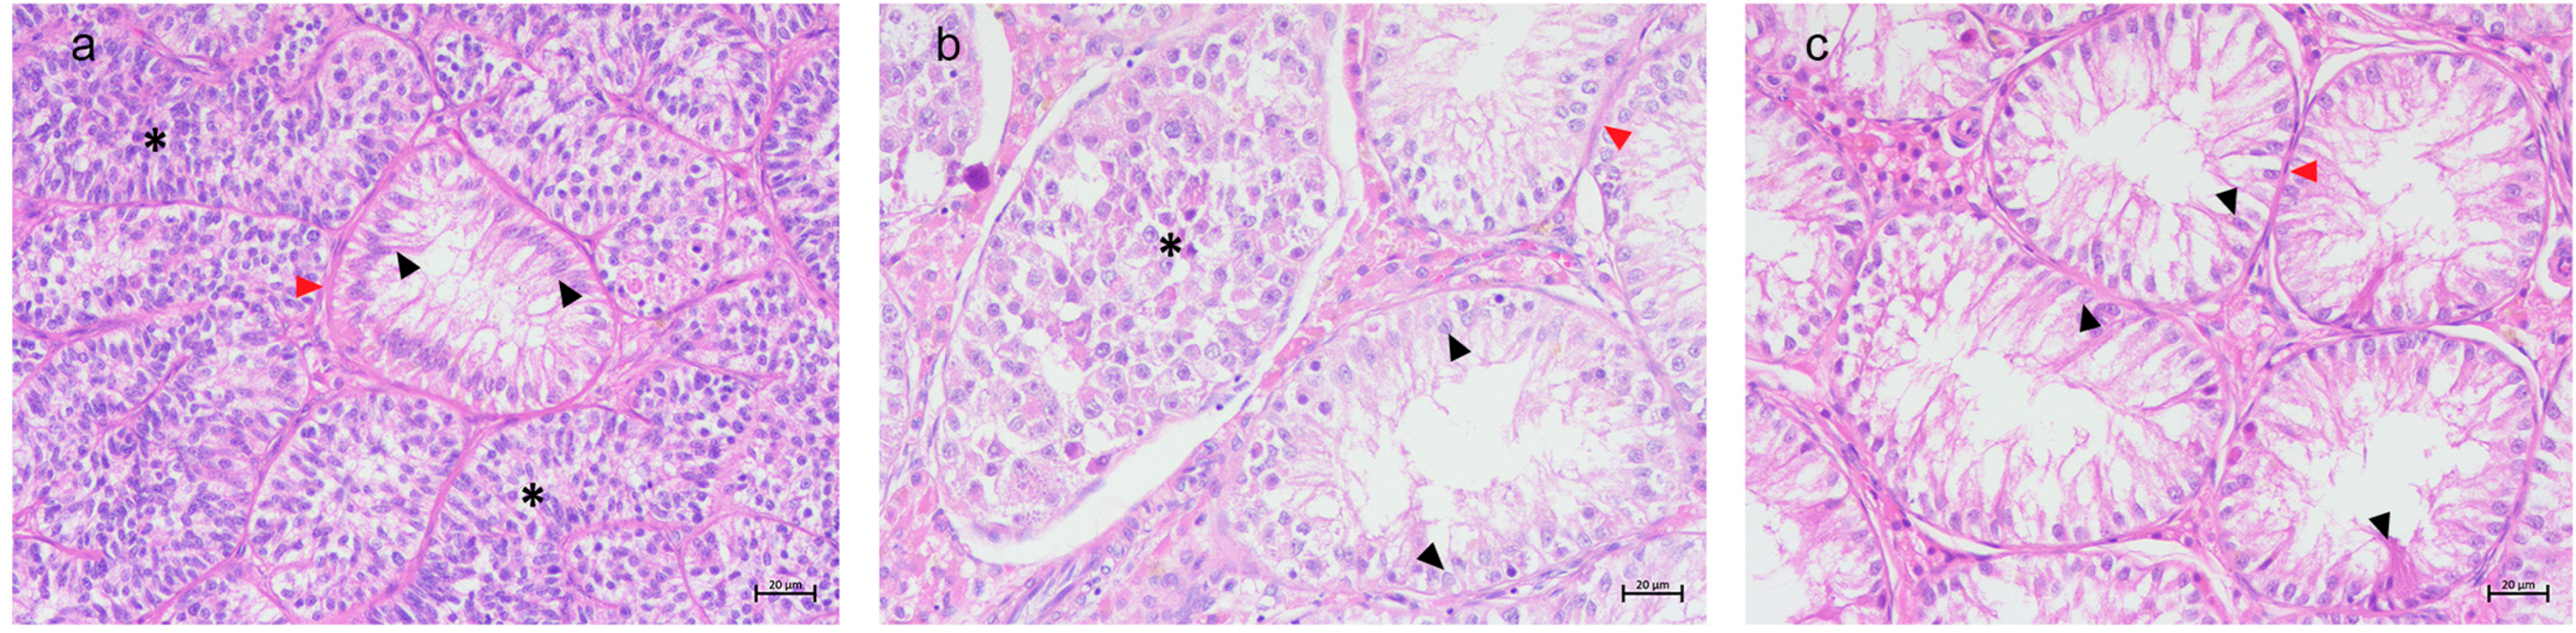

3.1. Histological Results